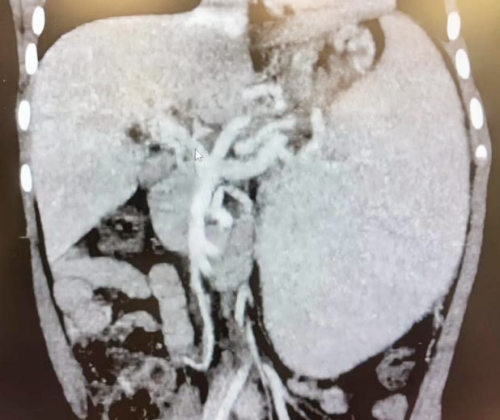

入院后,小儿外科为患儿开展了全面检查:影像学检查显示,患儿门静脉主干海绵样变性,肝门区大量侧支循环,脾脏重度增大,食管胃底静脉重度曲张;实验室检查提示血小板减少、凝血功能异常。结合患儿病史与检查结果,最终诊断为门静脉海绵样变伴门静脉高压。

为确保手术万无一失,多学科团队制定了周密的手术方案及应急预案:术前,放射科与超声医学科通过超声及CT血管三维重建,精准评估病变及血管发育情况;消化内科介入团队行选择性静脉造影,绘制"血管地图"精准定位;麻醉科与重症医学科提前做好风险防控,为手术全程保驾护航。

术前CT血管影像评估:门静脉主干阻塞、肝门血管海绵样变、脾大